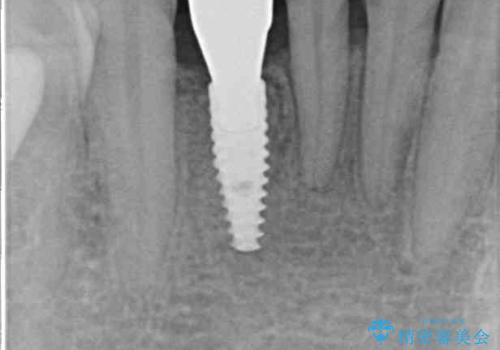

初診の状態ではすぐにでも抜けそうな状態で、インプラントによる補綴治療を行うこととしました。

抜歯後にスペースができると恥ずかしいため、抜歯した歯を接着剤で固定した上で矯正治療を行い、その後インプラントやオールセラミッククラウンの装着を行うこととしました。